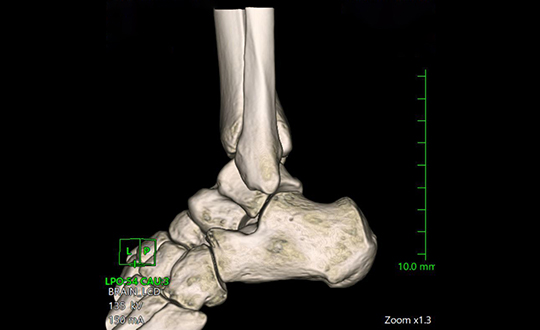

高速・高精細撮影により短時間で体内を詳しく撮影できるCT装置。80列検出器による高速撮影とAIDR 3D Enhanced技術で被ばくを低減し、安全性と精度の高い検査を行います。

関節疾患、スポーツ障害、骨折など、幅広い症例に対応可能で、患者様一人ひとりに合わせた治療方針を提案しています。術前検査から術後フォローまで一貫した対応が可能であり、地域の先生方との連携のもと、必要な症例に対し迅速かつ的確に対応します。